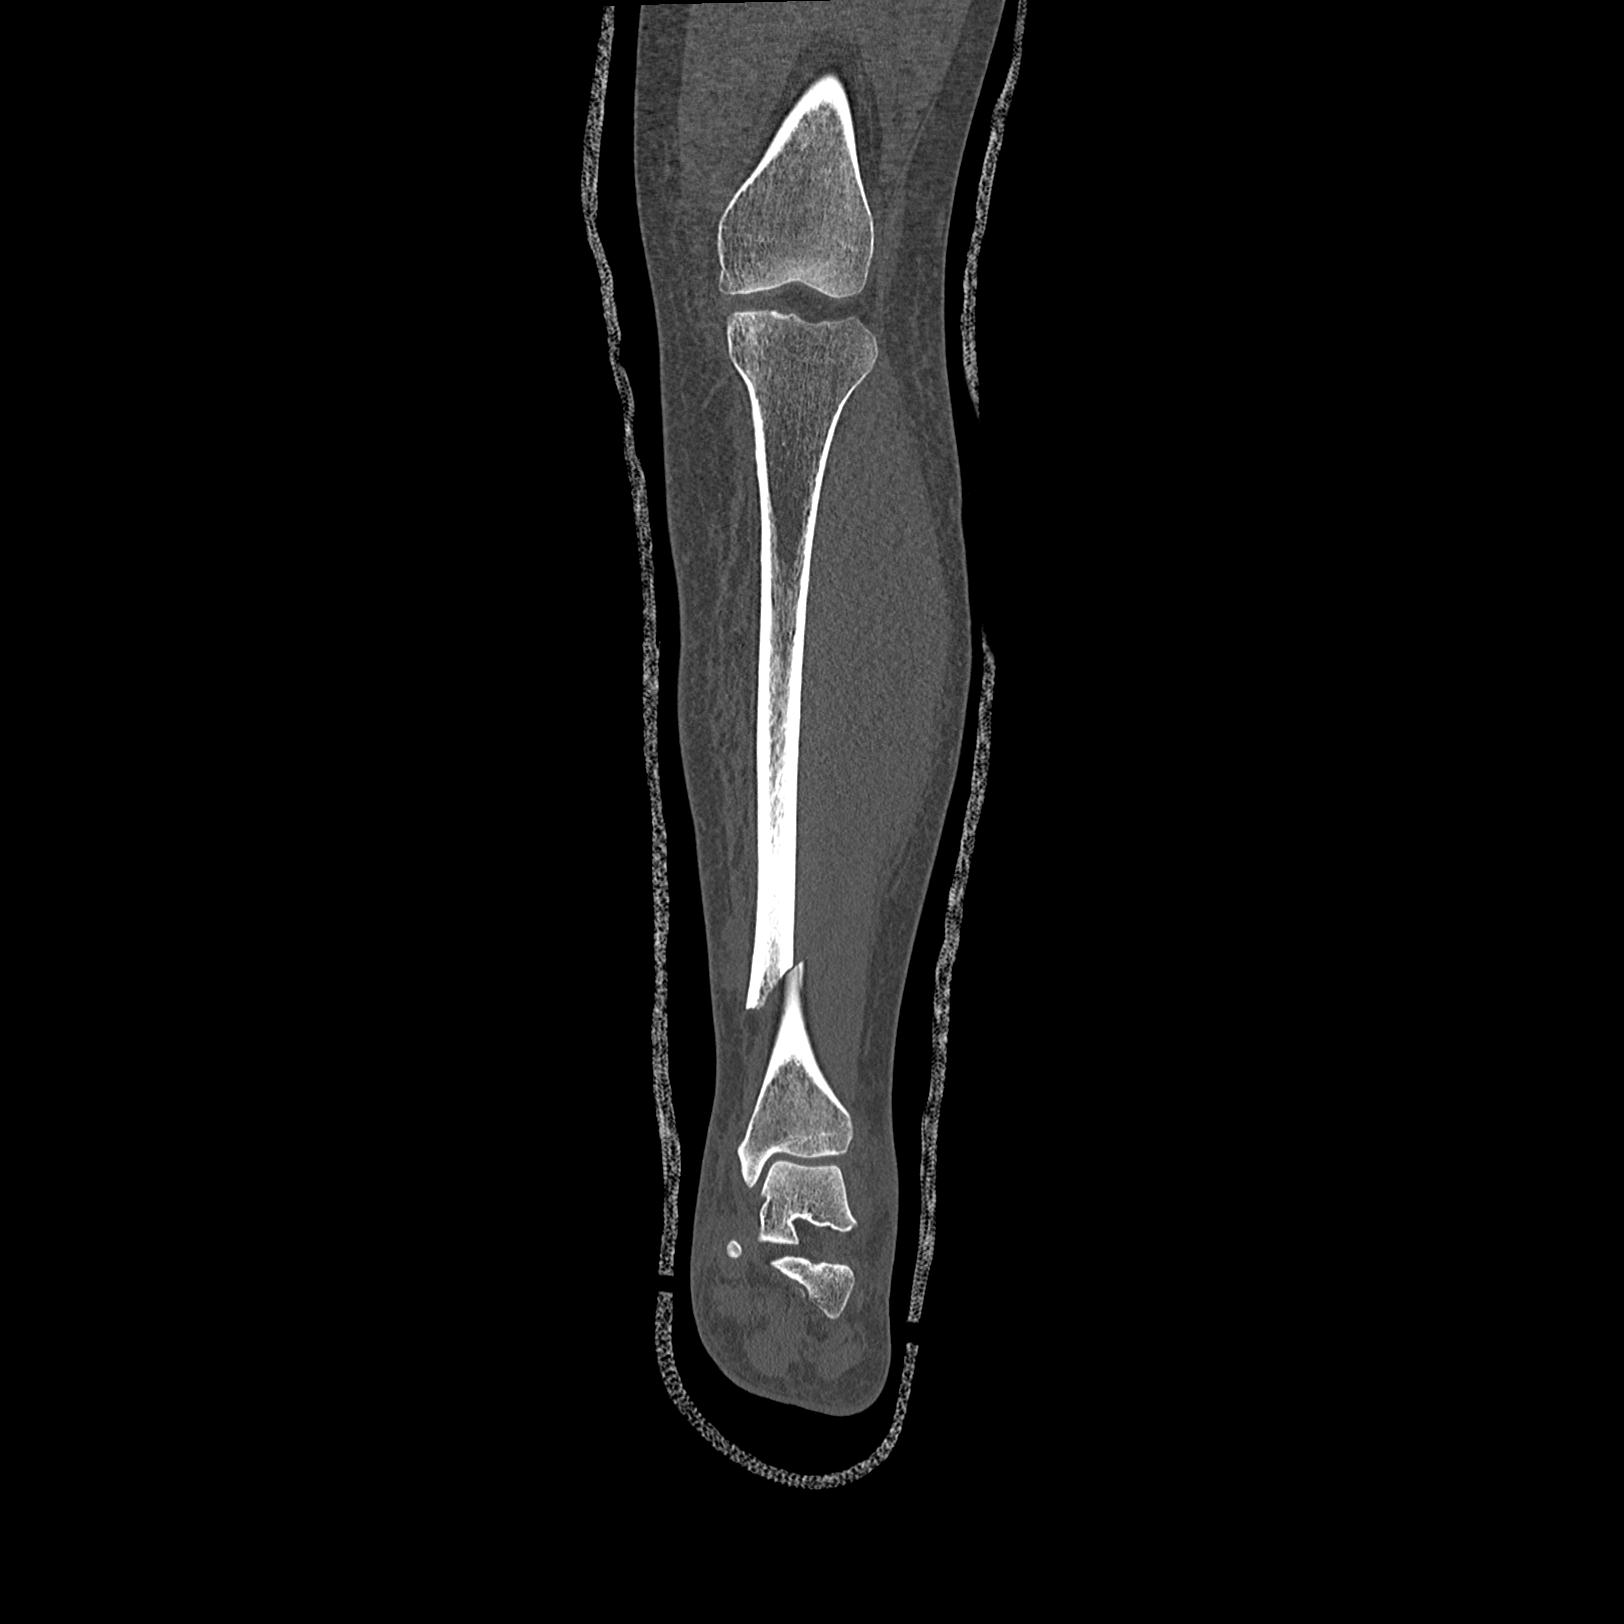

110211 1/6 1/8 左前腕 4R 15歳男性 橈骨骨幹部骨折